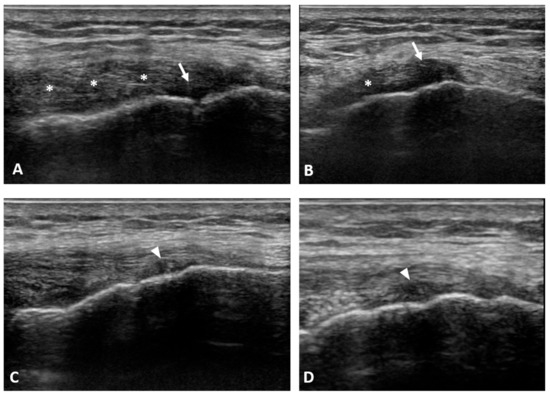

2. Materials and Methods

3. Results